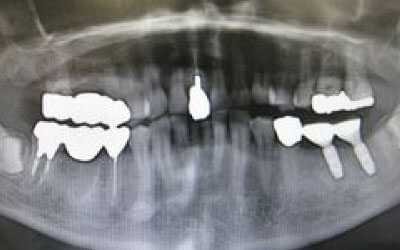

歯科の統計データをお伝えします。インプラントは、10年後に90~95%の確率で残ります。

対して、ブリッジは10年後に30~35%の確率で残っていると言われています。

ブリッジが失敗する場合、ほとんどが支えとなっている歯がダメになり、その結果抜歯が必要になることが多いです。

CTでは、骨や歯の状態を三次元で確認でき、正確な距離を測定することができます。

骨の厚さや傾き、神経の位置などを事前に詳しく計測することで、安全にインプラントを行うことができます。

しかし、事前にCTでしっかりと撮影し、三次元的に神経との距離を計測して治療計画を立てることで、心配は不要です。

また、当院では削りすぎを防ぐためのストッパーも使用しています。